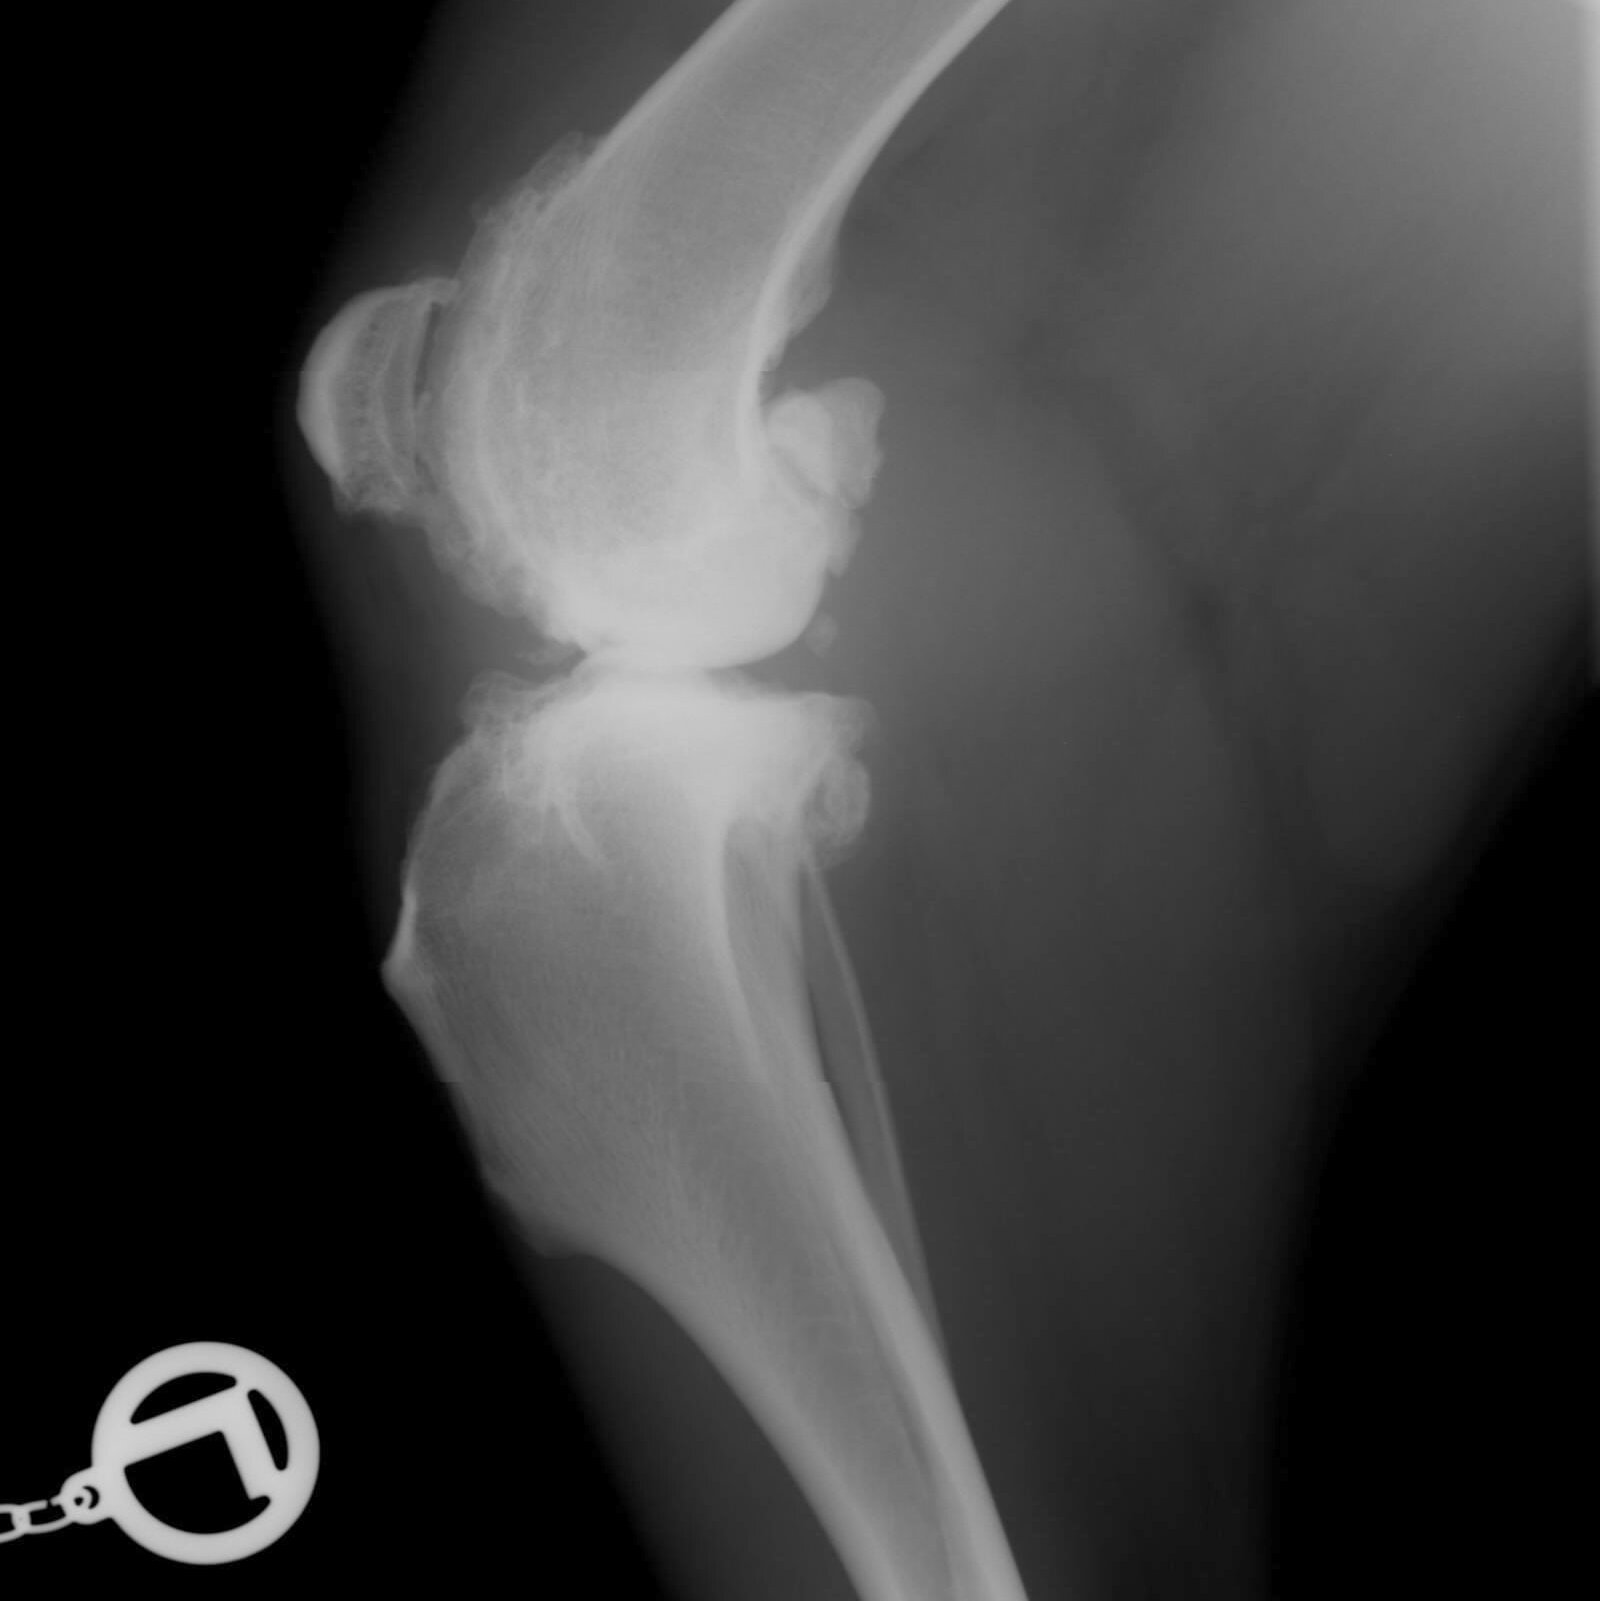

Wenn’s nimmer läuft – Arthrose beim HaustierAus der Tiermedizin

Arthrose – verschont bleibt fast keinerWenn die Gelenke und Knochen Probleme machen